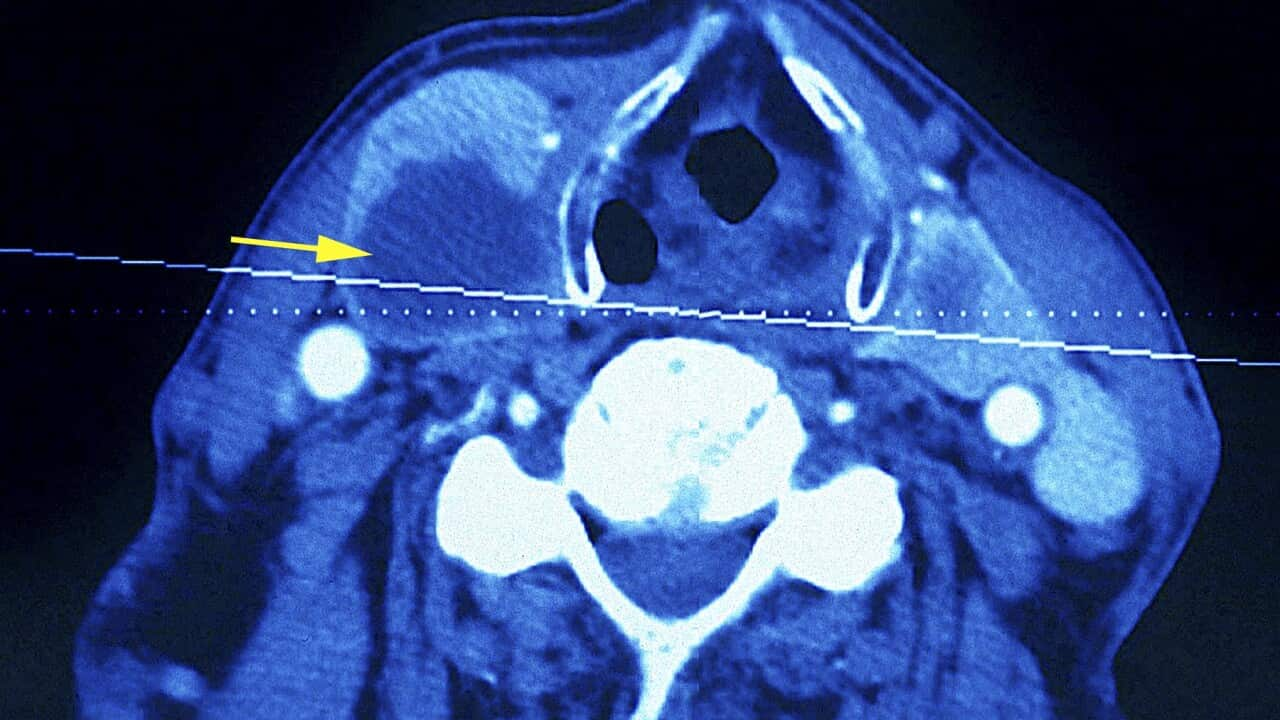

Thyroid Carcinoma. Thyroid Tumor. Ct Scan Of Neck. (Photo By BSIP/UIG Via Getty Images) Source: Universal Images Group Editorial